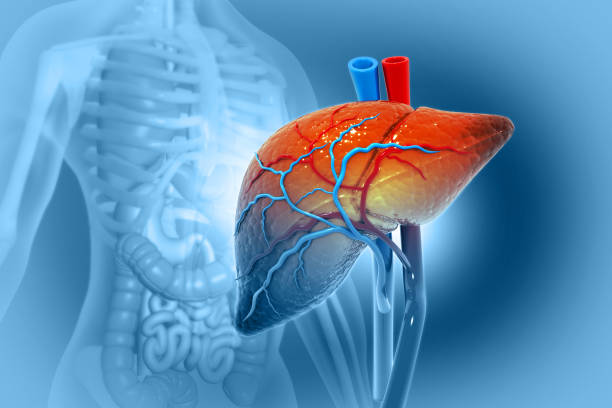

Book your appointment now with our doctor who is the best hepatoblastoma surgeon in mumbai.one of the Children who develop hepatoblastoma, a rare form of liver cancer, are affected. It is the most prevalent type of paediatric liver cancer and mostly affects those under the age of three. A extremely uncommon form of liver cancer called hepatoblastoma often strikes children between the ages of 1-3. The medical system uses chemotherapy and surgery, including liver transplantation, to treat hepatoblastoma. Five years after diagnosis, 75-80% of children with hepatoblastoma are still alive. The most prevalent age range for hepatoblastoma in children is from infancy to around five years old. In the first 18 months of life, most cases take place.Visit to our clinic and consult with our dcotor who is the best hepatoblastoma surgeon in mumbai

Hepatoblastoma's precise causation is unknown, but there are signs that it may be related to both hereditary and environmental factors. Hepatoblastoma is more likely to occur in kids with specific genetic disorders like Beckwith-Wiedemann syndrome or familial adenomatous polyposis.Our doctor kant shah is one of the best hepatoblastoma surgeon in mumbai who says that the Hepatoblastoma signs and symptoms can include nodules or swelling, stomach pain, and jaundice. It is critical to schedule an appointment with a doctor right away if your child exhibits any of these signs.

Chemotherapy, radiation therapy, and surgery are frequently used to treat hepatoblastoma. The stage of the disease, the child's general health, the size, and the placement of the tumour all affect the treatment plan. Surgery is the main form of treatment for hepatoblastoma, with the goal of entirely removing the tumour. Sometimes it can be necessary to remove the liver entirely or in part. A minimally invasive procedure, such as robotic or laparoscopic surgery, results in less pain and scarring, a speedier recovery, and a lower risk of complications.Contact us now for the best hepatoblastoma surgeon in mumbai.

After The SurgeryAfter surgery, radiation therapy and chemotherapy may be used to eradicate any cancer cells that may still be present. While chemotherapy uses chemicals to destroy cancer cells, radiation therapy uses high-energy X-rays to do the same. The specific treatment plan depends on the stage of the cancer.If the tumour is only in the liver and can be completely removed surgically after chemotherapy, the survival rate is over 80%.Three to five years after diagnosis, the survival rate for children whose cancer has spread beyond the liver or affected the entire liver is between 20 and 70%.This is about after surgery happens which is defined by our doctor who is the best hepatoblastoma surgeon in mumbai.